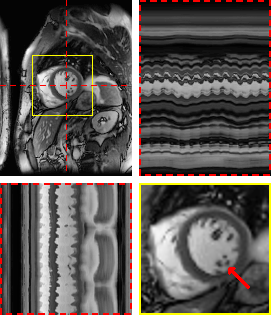

Figure 5: Exemplary free-breathing single-shot LGE reconstructions. Each sub-figure illustrates one frame, temporal profiles, and a close-up of the heart. Red arrows show details that are better visible in M-DIP compared to LR-DIP.

Figure 4 and Figure 5 illustrate the results for an exemplary real-time cine dataset and a free-breathing single-shot LGE dataset, respectively. Scoring results are given in Table 3 and Figure 6. M-DIP achieved highest scores in all considered criteria. Sharpness of real-time cines was scored significantly higher in M-DIP than in any other method. M-DIP and CineVN were scored equally in terms of noise/artifacts in the real-time cines, where only L+S received significantly lower scores than the other methods. In free-breathing single-shot LGE, M-DIP was scored significantly higher than both LR-DIP and L+S. Cine reconstruction took approximately 30 min with M-DIP and 45 min with LR-DIP, while LGE reconstruction took approximately 15 min with M-DIP and 10 min with LR-DIP.

Refer to caption

(a) M-DIP

(b) LR-DIP

(c) L+S

In a further in-vivo study, we applied M-DIP to free-breathing single-shot LGE data, thus demonstrating our method’s suitability for dynamic applications beyond cine imaging. The clarity of myocardial features was rated highest in the M-DIP reconstructions, with a substantial performance gap over LR-DIP and L+S. Similar to real-time cine, LR-DIP reconstructions are blurred, while L+S reconstructions exhibit high levels of noise.